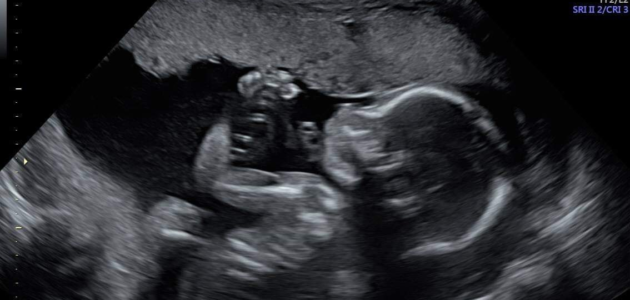

در مرحله اول ژل سرد بر روی شکم فرد زده می شود و با حرکت پروب بر روی شکم تصویر جنین را بر روی صفحه نمایشگر نشان می دهد. در این مرحله پزشک به بررسی اندام های جنین می پردازد.

قسمت های نرم بدن به رنگ خاکستری دیده می شود، استخوان های جنین سفید رنگ و مایع آمنیوتیک اطراف جنین در تصویر سونوگرافی سیاه رنگ است.